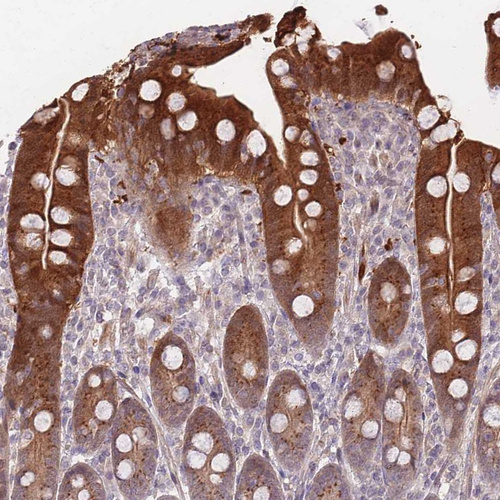

Immunohistochemical staining of human duodenum shows strong cytoplasmic positivity in glandular cells.